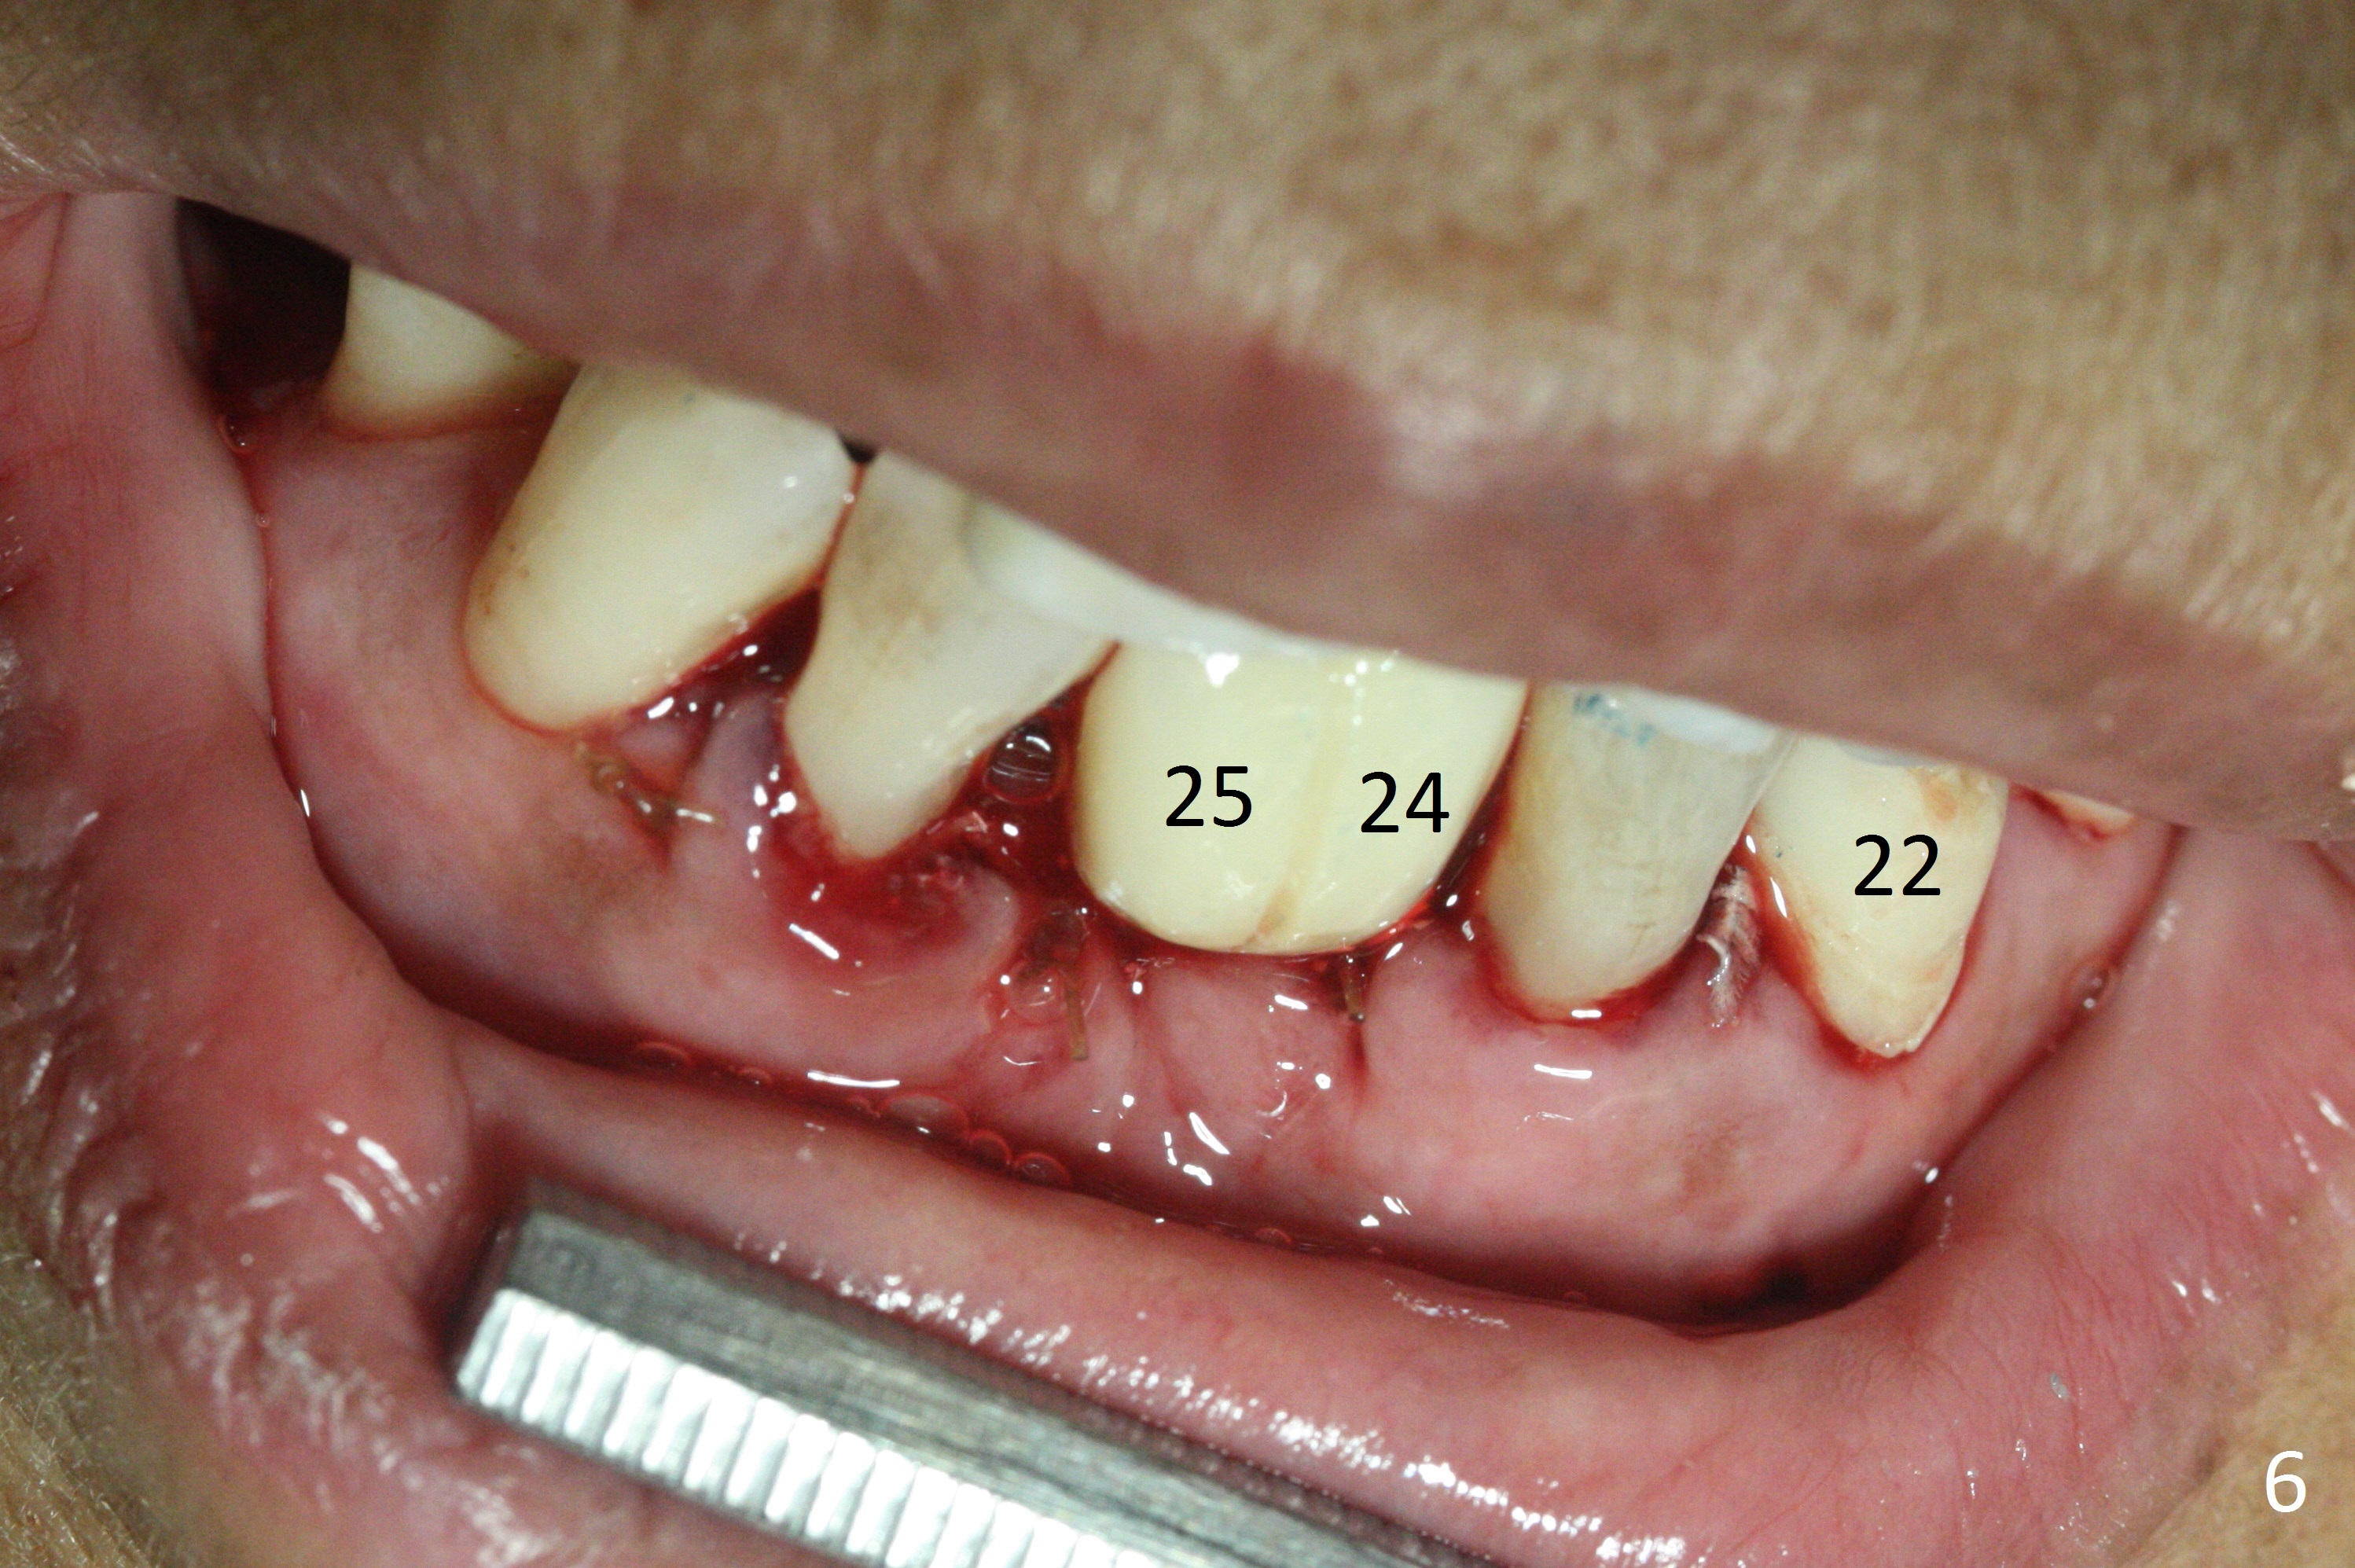

The depth of the osteotomy at #22 is 2-3 mm more than the expected implant length (Fig.2 with 2.7 mm drill in place). The implant at #22 (3.8x18 mm with insertion torque more than 50 Ncm) has clearance from the Incisive Canal and Mental Loop (Fig.3 red dashed line). Allograft with Osteogen is placed around the implants (Fig.4 *) in addition to Osteogen plug (cut in a thin layer) placed against the buccal wall of the socket at #22 (potential leakage). After suturing (Fig.5) and provisional cementation (Fig.6), periodontal dressing is applied (Fig.7). The implants seem to be ready for impression 4 months postop (Fig.8).